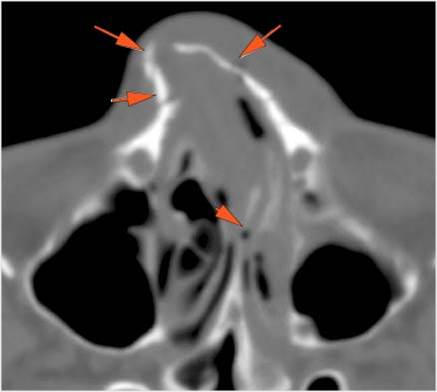

The mesial naso-orbito-ethmoid complex is fractured. Specifically, there is bony injury of the nasal bones or the frontal process of the maxilla and the medial walls of the orbit are abnormal. |

Yes | NA |

There is injury of the ethmoid complex. Specifically, the ethmoid roof, olfactory fossa and the cribriform plate are fractured and/or significantly dehiscent. |

The frontal bone and frontal sinus inner and outer tables are fractured. |

The circumferential extraconal and the intraconal orbital fat are edematous. |

Proptosis is present. |

There is evident general optic sheath swelling or swelling at the junction of the globe and sheath to suggest an optic sheath hematoma. |

LeFort type III, orbital zygomatic and orbital floor and fronto - naso-ethmoidal complex fractures with possible injury optic nerve/sheath - extent described above.